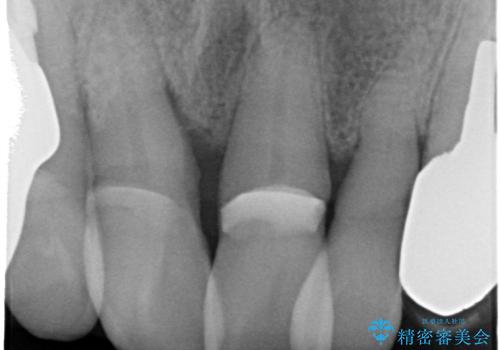

精査したところ、右上の前歯はかなり動揺があり保存できない状態でした。

右上の前歯の抜歯を行い、ブリッジの仮歯を入れ、動揺が無くなるのを確認した後、ジルコニアクラウンブリッジを入れました。

抜歯をしてからすぐに最終的な被せ物を入れるのではなく抜歯窩がしっかり治るのを待ってから最終的な被せ物を入れていきます。